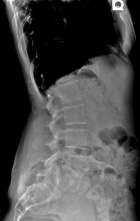

45 year old female with three month history of pain in low back radiating to left lower extremity

Zoom image: Radiological image Radiological image.